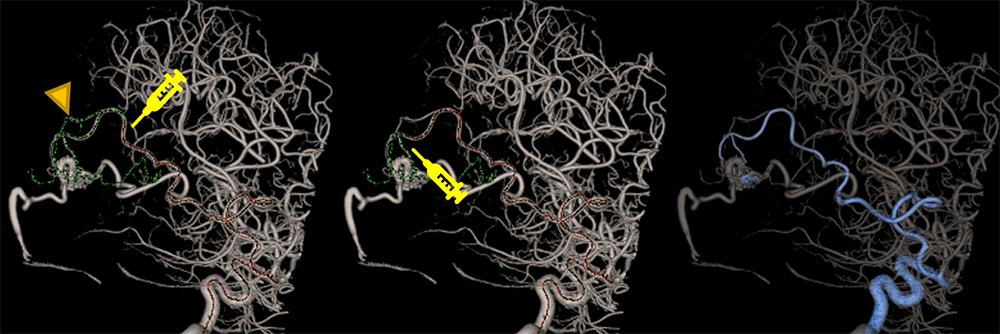

“Embo ASSIST with Virtual Injection”はCone Beam CTの再構成画像を用いて目的血管への経路を”可視化”できる有用なアプリケーションである.こちらもPost Processでの使用が可能である.AVM(Cerebral Arteriovenous Malformation)の様にFeederが多くFeederの特定に時間を要する症例にはもってこいのアプリケーションである.AVMの治療ではCBCTの情報を元に目的塞栓部位に繋がるFeederまでカテーテルを誘導する必要がある.カテーテルを目的のFeederまで誘導するために数回テスト・インジェクションを行い目的塞栓部位に繋がっているかを確認する必要があり造影剤使用量・被ばく量を増やしてしまう.また目的塞栓部位までカテーテル誘導する際に目的としない血管へ迷入する事で血管を損傷してしまうリスクも生じる. ”Embo ASSIST with Virtual Injection”の”Virtual Injection”機能はVR(Volume Rendering)またはMPR(Multi Planar Reconstruction)上でマウスカーソルを血管に合わせるとそこから造影されるであろう血管を描出し,仮想的にテスト・インジェクションを行った状態を再現してくれる. マウスカーソルがカテーテルの先端を意味し,マウスカーソルのproximalを赤線,distalを緑線で表現し,緑線が造影されるであろう血管となっている.”Virtual Injection”を使うことでどこまでカテーテルを進めて塞栓したらよいのかシミュレーションを行うことが出来る.また,シミュレーションした結果を色分けして保存することが可能である(図4).

IGS630_Tokaidaigaku_04.png

図4. “Virtual Injection”を使用した塞栓ポイント検討

左:塞栓ポイントが近位部のためfeeder以外も描出.

中央:塞栓ポイントを遠位部に移動でfeederのみ描出.

右:色分けによるセグメンテーション.